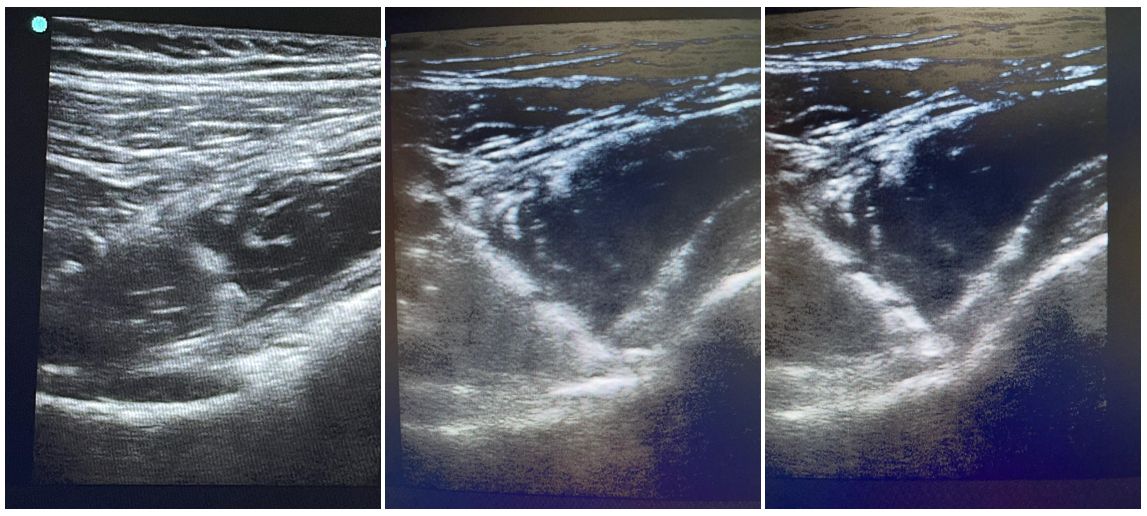

Imatges de l’administració eco-guiada de monòcits

Els monòcits són cèl·lules sanguínies immunitàries que juguen un paper clau en el desenvolupament i reparació dels teixits. El procediment consisteix en l’extracció de sang perifèrica, el seu processament en condicions d’esterilitat per a l’obtenció dels monòcits, i finalment l’administració eco-guiada d’aquests en la localització anatòmica lesionada.